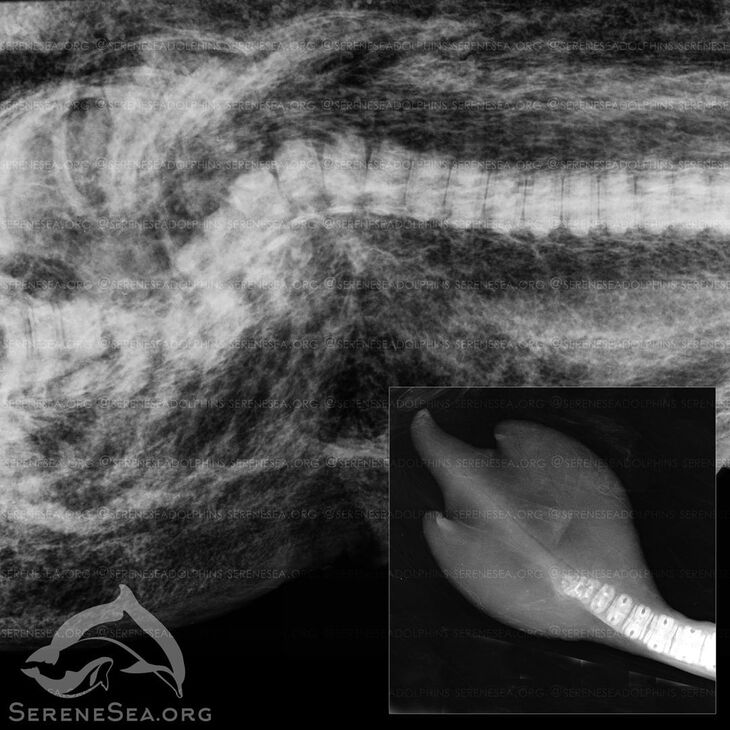

«Эта особенность развития ранее не встречалась в научной литературе по китообразным, но, как мы и предполагали, в Черном море такой дельфин не один. На рентгенографии, помимо особенности строения лопастей, было выявлено сращение хвостовых позвонков. Особенности этих двух дельфинов имеют схожую природу, – не исключено, что они являются родственниками, а врождённая аномалия может быть результатом генной мутации», — отметили в центре «Безмятежное море».

Обзорный рентген тела найденного в Алуште дельфинёнка выявил перелом позвоночника со смещением, полученный от тупого удара, что привело к смерти особи. В других морях травмы такого характера нередко фиксировались у детенышей, которым не повезло стать мишенью для взрослых агрессивно настроенных самцов.